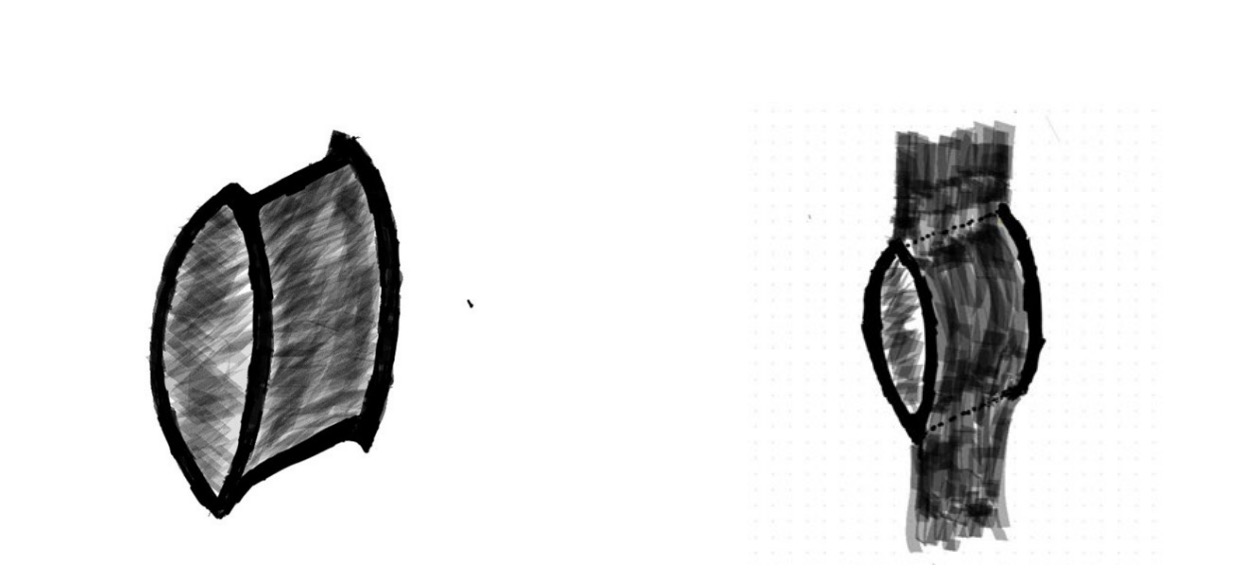

Para su ejecución se dispone de dos elementos cordonales de distinto calibre; el elemento más fino se utiliza para unirse al de mayor grosor. Se posicionan ambos cabos de forma paralela. Se realiza un ojal en el medio del elemento grueso, en el punto señalado para realizar el cruce de ambos (Figs. 1 y 2).

El primer elemento, de menor calibre, se introduce en el espesor del segundo y lo atraviesa hasta formar un asa o bucle (Figs. 3-5).

Se pasa por dentro del lazo hasta atrapar el extremo libre del grueso. Una vez atrapado, se desliza con un trayecto inverso, hasta volver a pasar por el lazo, se cruzan ambos y se finaliza así el lazo transfixiante. Esta asa será la que rodeando al segundo elemento lo envolverá con la imagen de lazada, lo que provoca la unión de ambos de una forma sólida y segura (Figs. 6-8).

El diseño del nuevo nudo debe considerarse del todo original, y puede ser utilizado para distintas aplicaciones tanto en el ambiente industrial en general como en el quirúrgico de la reparación tendinosa, como se explicará en el desarrollo de este trabajo (Figs. 9 y 10).